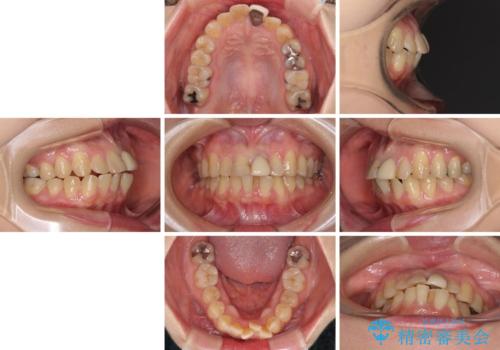

前歯のデコボコをワイヤー矯正できれいに整える

- 前歯のデコボコと変色した前歯を気にして来院された患者様です。

抜歯矯正により口元を引っ込めることも検討しましたが、特に口元の突出感は気になっていないとのことで、非抜歯にてワイヤー装置で矯正治療を行うこととしました。

気になっていた前歯の変色も、矯正治療後にオールセラミッククラウンにて補綴治療を行うこととしました。

舌の突出癖により治療期間中に開咬となり、治療が長引きましたが、口元も治療前よりも引っ込めることができ、すっきりとした仕上がりとなりました。